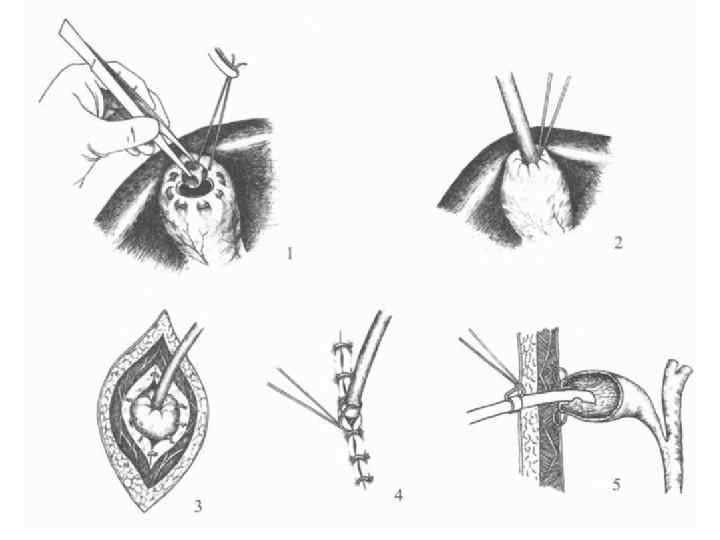

Дәстүрлі холецистоэктомия

Кіші жолмен жасалатын холецистоэктомия Көрсеткіштері: - жедел калькулезді холецистит - холецистолитиаз, холедохолитиаз, кеңеймеген; -ЛХЭ кезіндегі техникалық қиыншылықтар. Қарсы көрсеткіштер: - іш қуысы ағзаларын интраоперационды ревизия жасау қажеттілігі; - Жайылған перитонит.

Вскрытие брюшины при ХЭ из МПД. Захват дна желчного пузыря окончатым зажимом. Субсерозное выделение желчного пузыря с помощью электрокоагуляции.

Инверсия выделенного на 2/3 желчного пузыря. Схемы дренирования после ХЭ из МПД